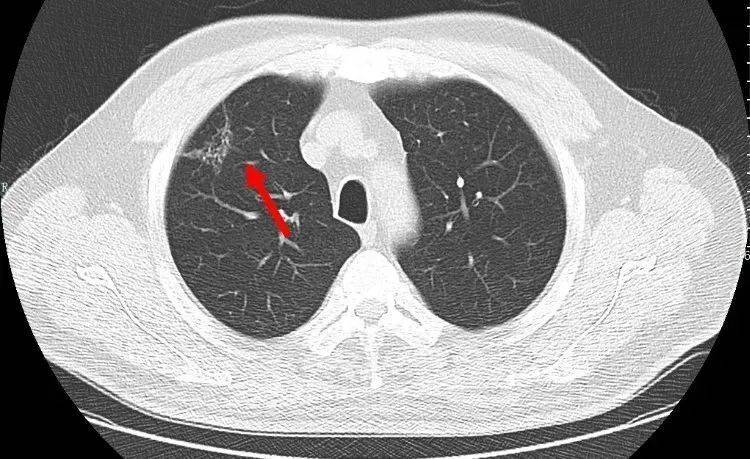

![中医治疗#肺癌# ,是如何一步一步好转的?【门诊案例,仅供参考,不可一概而论,如有问题,须由专业医生问诊之后开方】郑女士 62岁 农民 患者在地里干活时出现胸背部疼痛剧烈,咳嗽,咳痰就赶紧去当地医院就诊行胸椎MRI显示:1.T5/6椎体及其右侧椎弓根异常信号;2.左侧胸腔积液。胸部CT显示:1.左肺门旁占位病变2.纵膈淋巴结多发转移2.双侧胸腔积液3.T5椎体右侧横突、椎弓根及第5、6后肋骨转移。考虑为肺癌骨转移在CT引导下行经皮左肺占位穿刺活检术,术后病理确诊为左肺腺癌。基因检测示:EGFR L858R 突变丰度27%,21因子突变。最终确诊为左肺腺癌;纵膈淋巴结转移,胸腔转移,多发骨转移做了放化疗和吃靶向药之后,患者身体承受不住,当地医院建议,找个好一点的中医调理一下,患者经过病友推荐,找到了我。【症状表现】胸背疼痛,咳嗽,痰少,喘促,痰中带血,乏力气短,面色苍白,纳差,舌淡红,有齿痕,舌苔白,脉细弱。【诊断结果】毒邪蕴结 气血虚弱证【诊治思路】益气补血,解毒抗癌经我开的方子调理之后,患者身体明显好转,胸腰背疼痛,咳嗽,痰中带血,症状消失。复查结果显示患者肺内、纵隔肿瘤,胸腔积液已经基本消失,各项指标均恢复正常,达到临床治愈。目前继续中医药并靶向治疗防止复发。郑女士的身体非常好,已与正常人无异,这样的结果让患者及家属都非常满意,开玩笑说要不是当初的这些片子,病理报告,甚至有些怀疑当初是误诊了呢![你好]我是肿瘤科医生武常生,擅长用中医的方法治疗肺结节、乳腺结节、甲状腺结节、肺癌、乳腺癌、肠癌、宫颈癌、卵巢癌等肿瘤结节问题,并且有多年的临床治疗经验【如果你有肺结节、乳腺结节、甲状腺结节、肺癌、乳腺癌、肠癌、宫颈癌、卵巢癌等结节肿瘤方面的问题,需要我的帮助,可以在评论区打“需要帮助”,帮你辨证分析】](https://wx2.sinaimg.cn/large/008oAFzaly1hlsytz68n3j30b407qdjd.jpg)

中医治疗#肺癌# ,是如何一步一步好转的?【门诊案例,仅供参考,不可一概而论,如有问题,须由专业医生问诊之后开方】郑女士 62岁 农民 患者在地里干活时出现胸背部疼痛剧烈,咳嗽,咳痰就赶紧去当地医院就诊行胸椎MRI显示:1.T5/6椎体及其右侧椎弓根异常信号;2.左侧胸腔积液。胸部CT显示:1.左肺门旁占位病变2.纵膈淋巴结多发转移2.双侧胸腔积液3.T5椎体右侧横突、椎弓根及第5、6后肋骨转移。考虑为肺癌骨转移在CT引导下行经皮左肺占位穿刺活检术,术后病理确诊为左肺腺癌。基因检测示:EGFR L858R 突变丰度27%,21因子突变。最终确诊为左肺腺癌;纵膈淋巴结转移,胸腔转移,多发骨转移做了放化疗和吃靶向药之后,患者身体承受不住,当地医院建议,找个好一点的中医调理一下,患者经过病友推荐,找到了我。【症状表现】胸背疼痛,咳嗽,痰少,喘促,痰中带血,乏力气短,面色苍白,纳差,舌淡红,有齿痕,舌苔白,脉细弱。【诊断结果】毒邪蕴结 气血虚弱证【诊治思路】益气补血,解毒抗癌经我开的方子调理之后,患者身体明显好转,胸腰背疼痛,咳嗽,痰中带血,症状消失。复查结果显示患者肺内、纵隔肿瘤,胸腔积液已经基本消失,各项指标均恢复正常,达到临床治愈。目前继续中医药并靶向治疗防止复发。郑女士的身体非常好,已与正常人无异,这样的结果让患者及家属都非常满意,开玩笑说要不是当初的这些片子,病理报告,甚至有些怀疑当初是误诊了呢![你好]我是肿瘤科医生武常生,擅长用中医的方法治疗肺结节、乳腺结节、甲状腺结节、肺癌、乳腺癌、肠癌、宫颈癌、卵巢癌等肿瘤结节问题,并且有多年的临床治疗经验【如果你有肺结节、乳腺结节、甲状腺结节、肺癌、乳腺癌、肠癌、宫颈癌、卵巢癌等结节肿瘤方面的问题,需要我的帮助,可以在评论区打“需要帮助”,帮你辨证分析】